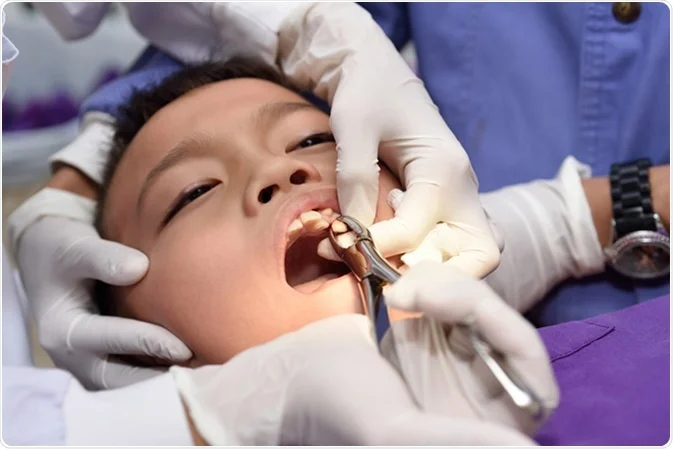

- Anesthesia: The dentist will administer a local anesthetic to numb the area around the tooth, ensuring that the patient is comfortable and pain-free during the procedure.

- Extraction: Using specialized dental instruments, the dentist or oral surgeon will gently loosen the tooth from its socket in the jawbone. For multi-rooted teeth, the tooth may be divided into sections to facilitate extraction.

- Removal: The tooth is carefully lifted and removed from the socket. In some cases, a small amount of bone may need to be removed.